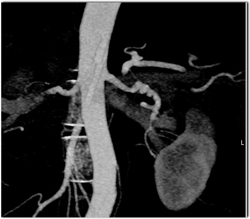

Hydronephrosis With Delayed Function